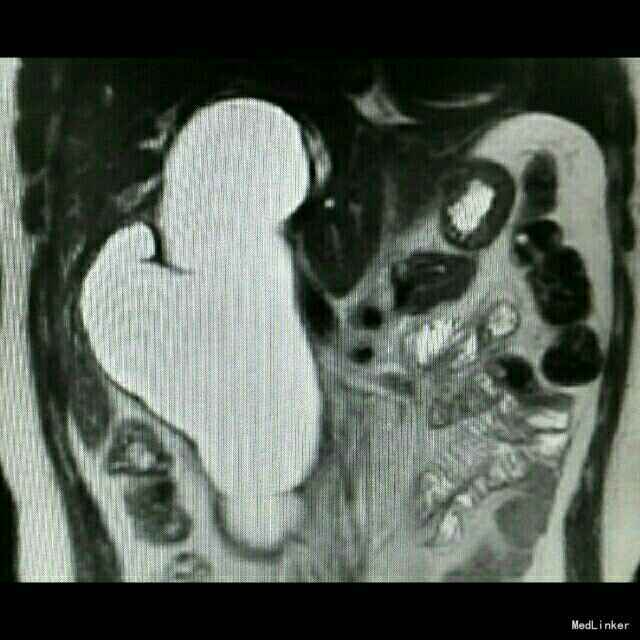

查体:皮肤巩膜轻度黄染 检查:B超示胆总管囊性占位,胆囊增大,肝内胆管扩张。MRCP:先天性肝外胆管囊肿,伴肝内胆管及胰管扩张,胆囊炎,右肝血管瘤可能。TB 65 umol/L;DB 41 umol/L; ALT 137U/L;AST74 U/L ;γ-GT366 U/L术后恢复正常。肿瘤指标正常。

诊断:先天性胆总管囊肿,慢性胆囊炎。 治疗:行胆总管囊肿切除+胆囊切除+胆道空肠Roux-en-y吻合术。术中腹腔未见积液,胆总管大小越25*8.5cm,囊壁较厚,胰头部受压明显,胆囊10*6*5cm。沿胆囊底打开胆囊浆膜,逆行游离至胆囊管汇入处,结扎胆囊动脉,打开肝十二指肠韧带,沿胆总管囊肿游离囊肿,保护肝动静脉及门静脉,向下游离至胰内胆管,于囊肿下端切断胆总管,结扎残端。向上游离至肝门部,于左右肝管汇合处离断,完整切除囊肿。距屈氏韧带25cm直线闭合器断空肠,游离远端空肠系膜行肝总管远端空肠段侧吻合。距胆肠吻合口远端45cm处,空肠与近端空肠残端以直线切割闭合行空肠侧侧吻合。间断缝合残端,吻合口放置引流管,关腹。术后加强白蛋白对症支持治疗,术后第5日开始进食流质。病理回报慢性胆囊炎。